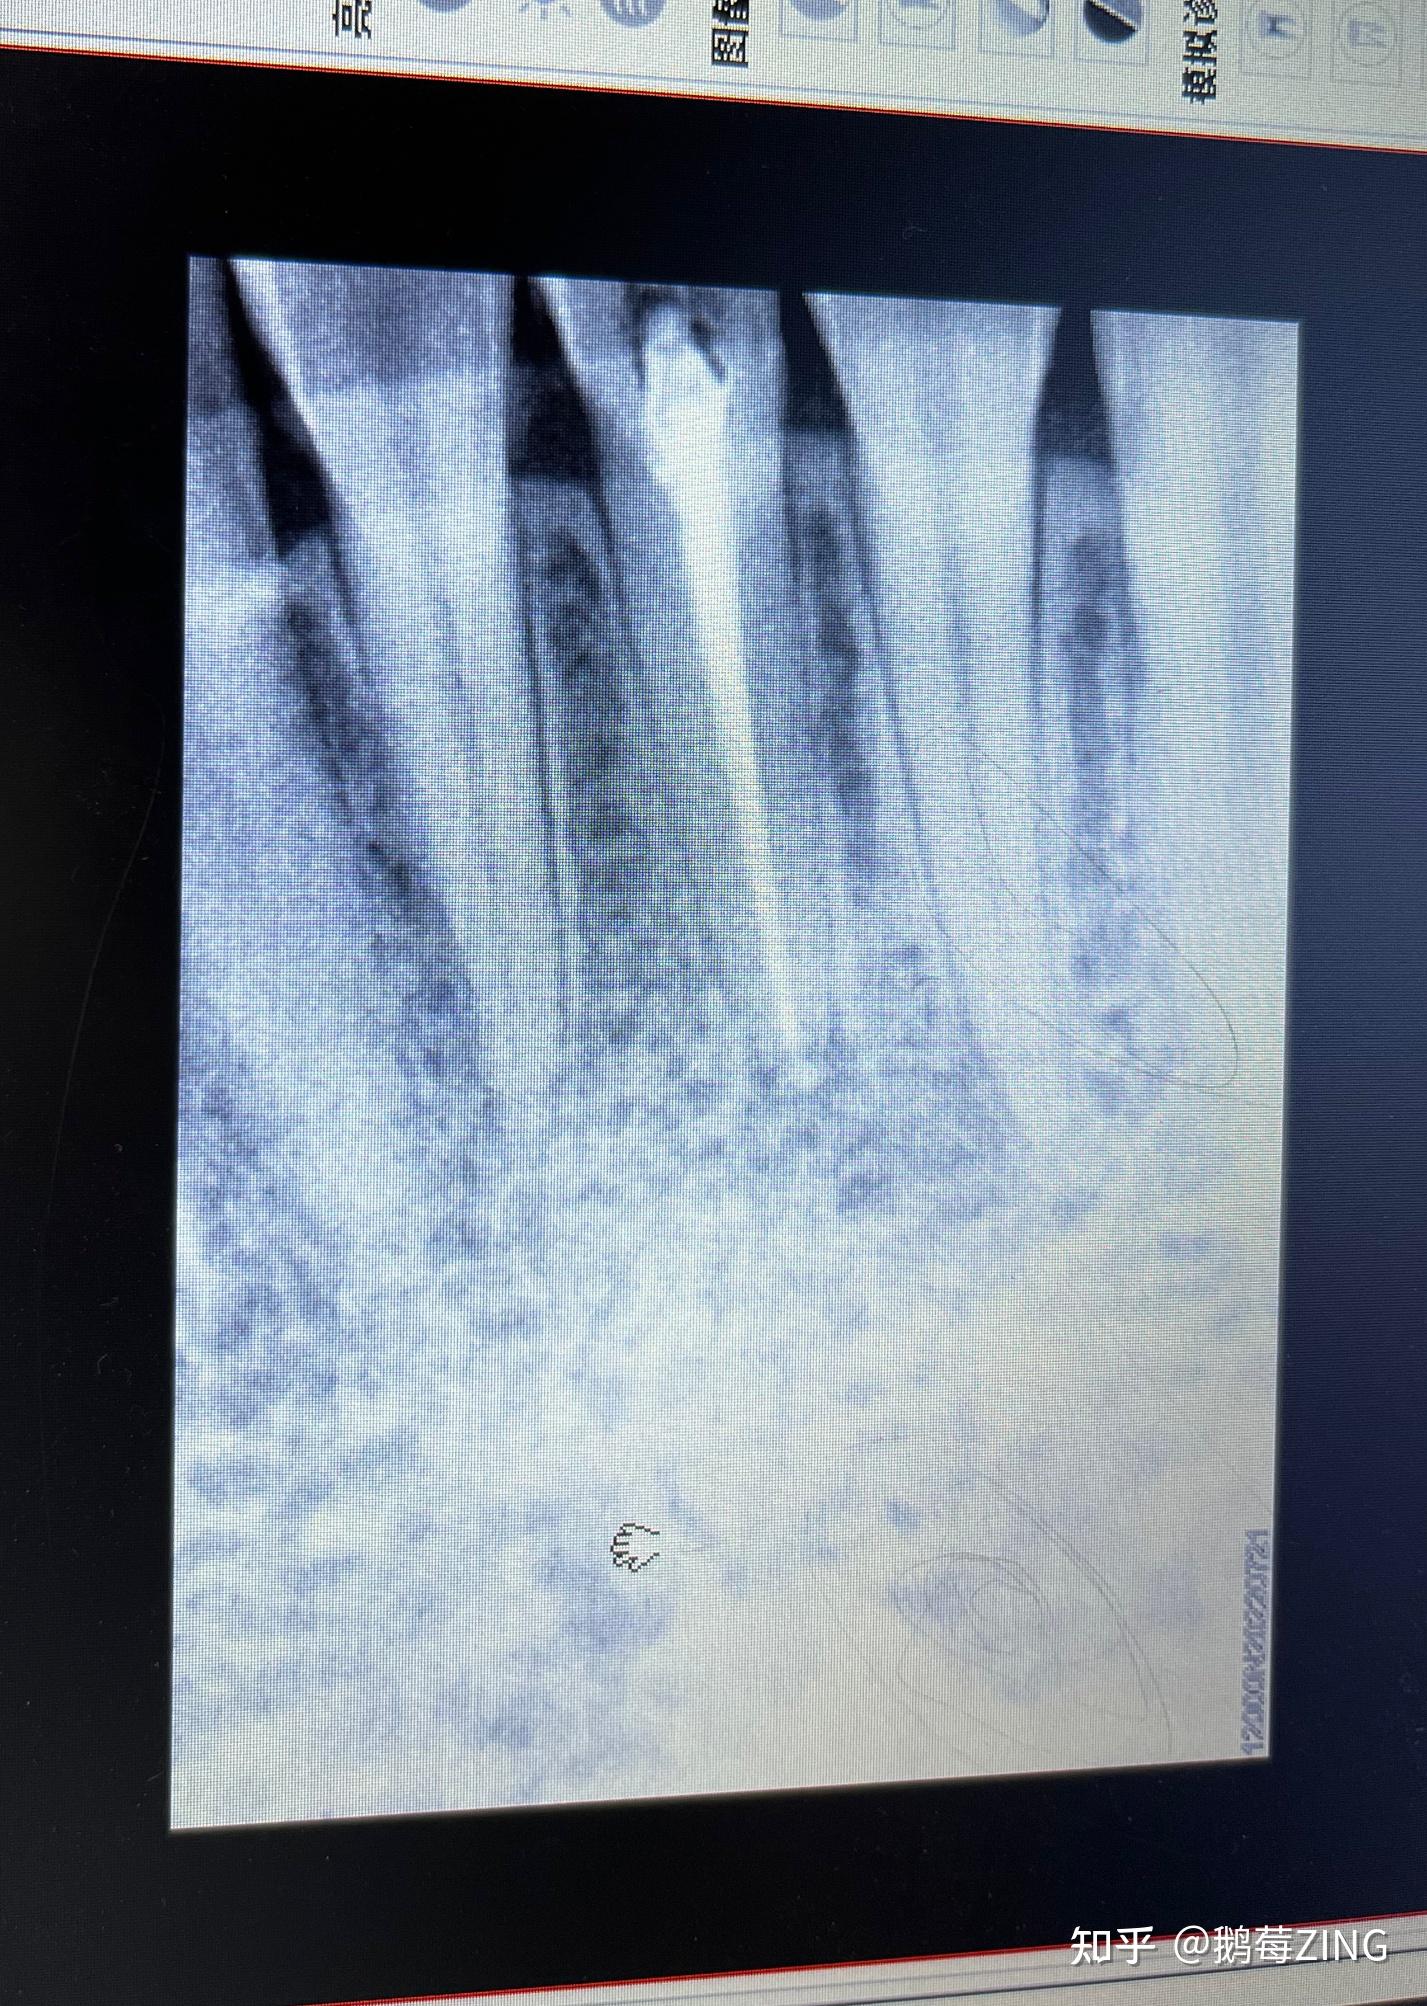

求助本人患牙根管治疗后发现又出现一根尖囊肿求助各位大佬能不能保牙

记录一次根尖囊肿之前期保守根管治疗